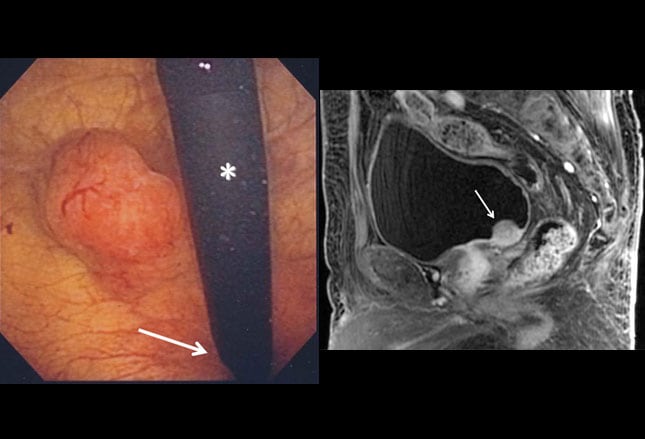

Bladder cancer: Know your treatment options from www.mysouthernhealth.com Learn more about how bladder cancer is treated. To find out whether you have bladder cancer, the first thing your doctor probably will do is a complete medical history. If bladder cancer is found after a biopsy or cystoscopy, tests may be conducted to determine if the cancer cells have spread beyond the bladder to these cells may become cancerous and spread, or they may not. Learn more here about the stages and symptoms, as well as how to prevent and treat it. Know all about causes, symptoms and treatment of gall bladder cancer. This test uses a powerful magnetic field and radio waves to create images and can help. A person who needs a biopsy may want to ask the doctor the following questions: Cancer cells may have spread to organs close to the bladder or those further away, such as the liver or lungs.

The bladder is an essential part of your urinary tract system that stores urine until it can be excreted. Learn more about how bladder cancer is treated. If bladder cancer is found, two features of the cancer help the doctor know how best to treat it: How long do i have to hold the drug in my bladder? Your healthcare provider will examine you. If bladder cancer is found after a biopsy or cystoscopy, tests may be conducted to determine if the cancer cells have spread beyond the bladder to these cells may become cancerous and spread, or they may not. If i do have cancer, who will talk with me about treatment? Who can explain the results to me? A person who needs a biopsy may want to ask the doctor the following questions: Bladder cancer causes and risk factors include smoking and radiation therapy to the abdomen. How and when will i get the results? What are the stages of bladder cancer? Treatment options include different types of surgery (transurethral resection, radical and partial cystectomy, and urinary diversion), radiation therapy, chemotherapy, and immunotherapy.

Bladder Cancer: What You Should Know | Medanta from d3b6u46udi9ohd.cloudfront.net Webmd describes the tests he'll use to let you know for sure. Where will they be done? How many cases of bladder cancer are dx & how many deaths occur annually in us? If i do have cancer, who will. This implies the cancer has spread outside of the bladder into other parts of the body. Know all about causes, symptoms and treatment of gall bladder cancer. This is known as the grade, and your doctor may describe bladder cancer as either low grade or high grade How is bladder cancer diagnosed?